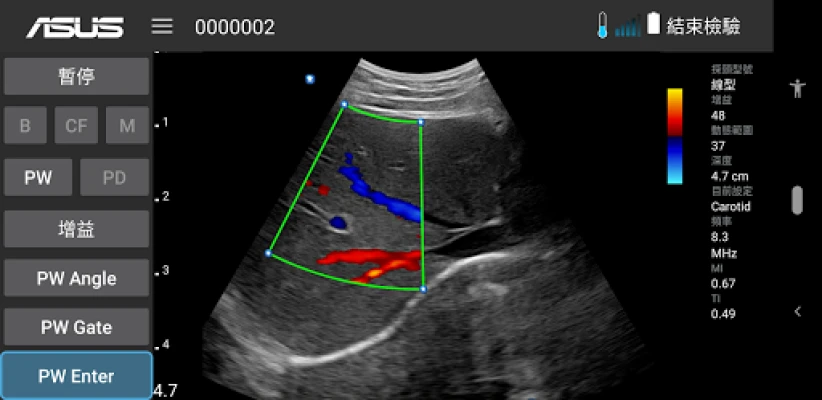

ASUS Portable Ultrasound is a wireless, handheld, pocket-sized imaging tool.

This flexible and feasible APP supports reliable and dependable images for diverse scenarios.